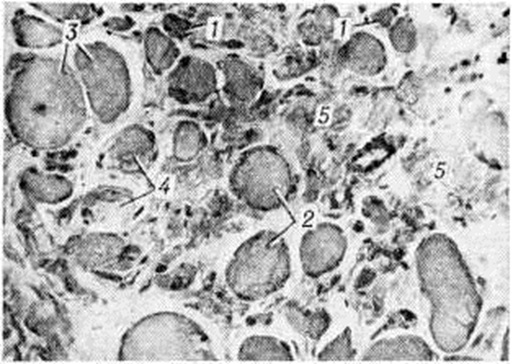

МиопатияМиопатия (греческий mys, my[os] мышца + -pathos страдание, болезнь) — группа наследственных заболеваний мышц, основными клиническими проявлениями которых являются мышечная слабость, атрофия, снижение мышечного тонуса, снижение или отсутствие сухожильных рефлексов, изменение биоэлектрической активности мышц. Первые клинико-морфологически описания заболеваний этой группы принадлежат Г. Дюшенну, Ж. Крювелье (1853), В. Эрбу (1883—1884), В. К. Роту (1876, 1895). Патология встречается во всех странах мира. Частота различных форм составляет 2—6 на 100 000 населения. Классификация Вопросы классификации Миопатия разрабатываются в различных направлениях. Миопатия классифицируют по типу наследования: аутосомно-рецессивные, аутосомно-доминантные, рецессивные и доминантные, сцепленные с Х-хромосомой. В зависимости от времени появления первых симптомов и характера течения Миопатия под разделяют на врождённую непрогрессирующую Миопатия и прогрессирующую мышечную дистрофию (ранняя детская, детская, юношеская и поздняя формы). Прогрессирующая мышечная дистрофия также подразделяется на формы в зависимости от преимущественной локализации миодистрофического процесса (например, плече-лопаточно-лицевая миодистрофия Ландузи — Дежерина, тазоплечевая миопатия Эрба — Рота, бульбарно-офтальмоплегическая Миопатия, дистальная Миопатия), характера распространения процесса восходящий и нисходящий варианты). В отдельную группу выделяют Миопатия с выраженной псевдогинертрофией мышц (псевдогипертрофическая миопатия Дюшенна, доброкачественная псевдогипертрофическая миопатия Беккера и другие). Этиология и патогенез Причиной заболеваний являются генетически детерминированные дефекты метаболизма мышечной ткани или структуры мышечных клеток. Поскольку первичный молекулярный дефект не известен ни для одной из форм Миопатия, патогенез детально не изучен. По-видимому, он не однозначен для всех форм Миопатия Известно, однако, что при всех заболеваниях этой группы в большей или меньшей степени выражены усиленный распад мышечных белков, преобладающий над их ускоренным, но неполноценным синтезом, изменения сосудов, нарушения проницаемости их стенок, нарушения структуры и проницаемости клеточных мембран, сдвиг обмена катионов, изменения в соединительной ткани и другие Предполагают, что при некоторых формах первичный молекулярный дефект локализуется не в самой мышечной ткани (а, например, в нервной) и служит лишь пусковым фактором указанных изменений. Возможно также, что при некоторых формах Миопатия эффект мутантного гена более генерализован и распространяется на мышечную, нервную и другие ткани. Патологическая анатомия Морфологически изменения при Миопатия характеризуются нарастающей атрофией скелетных мышц, которые уменьшаются в объёме и становятся плотными, бурого цвета вследствие разрастания соединительной ткани или, напротив, увеличиваются в объёме за счёт жировой клетчатки. При различных формах мышечных дистрофий (псевдогипертрофических, плече-лопаточно-лицевой, тазоплечевой, офтальмоплегической, бульбарно-офтальмоплегической) определяются в основном однотипные гисто л. изменения (рисунок 1): уменьшение количества мышечных волокон в пучках, резкая диффузная разнокалиберность сохранившихся волокон с преобладанием среди них атрофированных, гиалиновая и вакуольная дистрофия в части мышечных волокон, дискоидный и коагуляционный некроз отдельных волокон, расщепление гипертрофированных волокон, разрастание соединительной и жировой ткани в эндо и перимизии. В некоторых мышечных волокнах находят саркоплазматические тельца, саркоплазматические массы, кольцевидные миофибриллы. Изредка встречаются регенерирующие волокна с круглыми сочными ядрами и богатой рибонуклеопротеидами саркоплазмой. Мышечные веретена длительное время остаются неизмененными. В части наблюдений выявляются периваскулярные лимфоидно-гистиоцитарные инфильтраты. По мере нарастания двигательных нарушений отмечается постепенное уменьшение количества мышечных волокон и нивелировка их диаметра за счёт резкого уменьшения количества и калибра гипертрофированных волокон. |

Наиболее быстро эти изменения развиваются при миопатии Дюшенна — злокачественном варианте псевдогипертрофической Миопатия. Для доброкачественного варианта — миопатии Беккера — характерно сочетание выраженных процессов липоматоза и склероза с резкой гипертрофией части мышечных волокон.

С последней особенностью связывают длительную компенсацию двигательных нарушений у таких больных. В далеко зашедшей стадии Миопатия определяются небольшие островки из атрофированных мышечных волокон на фоне резкого склероза и липоматоза эндои перимизия (рисунок 2), при этом гистологически не представляется возможным дифференцировать Миопатия с нейромышечной атрофией. У пробандов при биопсии мышц находят единичные атрофированные мышечные волокна преимущественно I типа, пролиферацию ядер с переходом их в центр волокна и незначительное увеличение соединительной ткани в эндомизии.